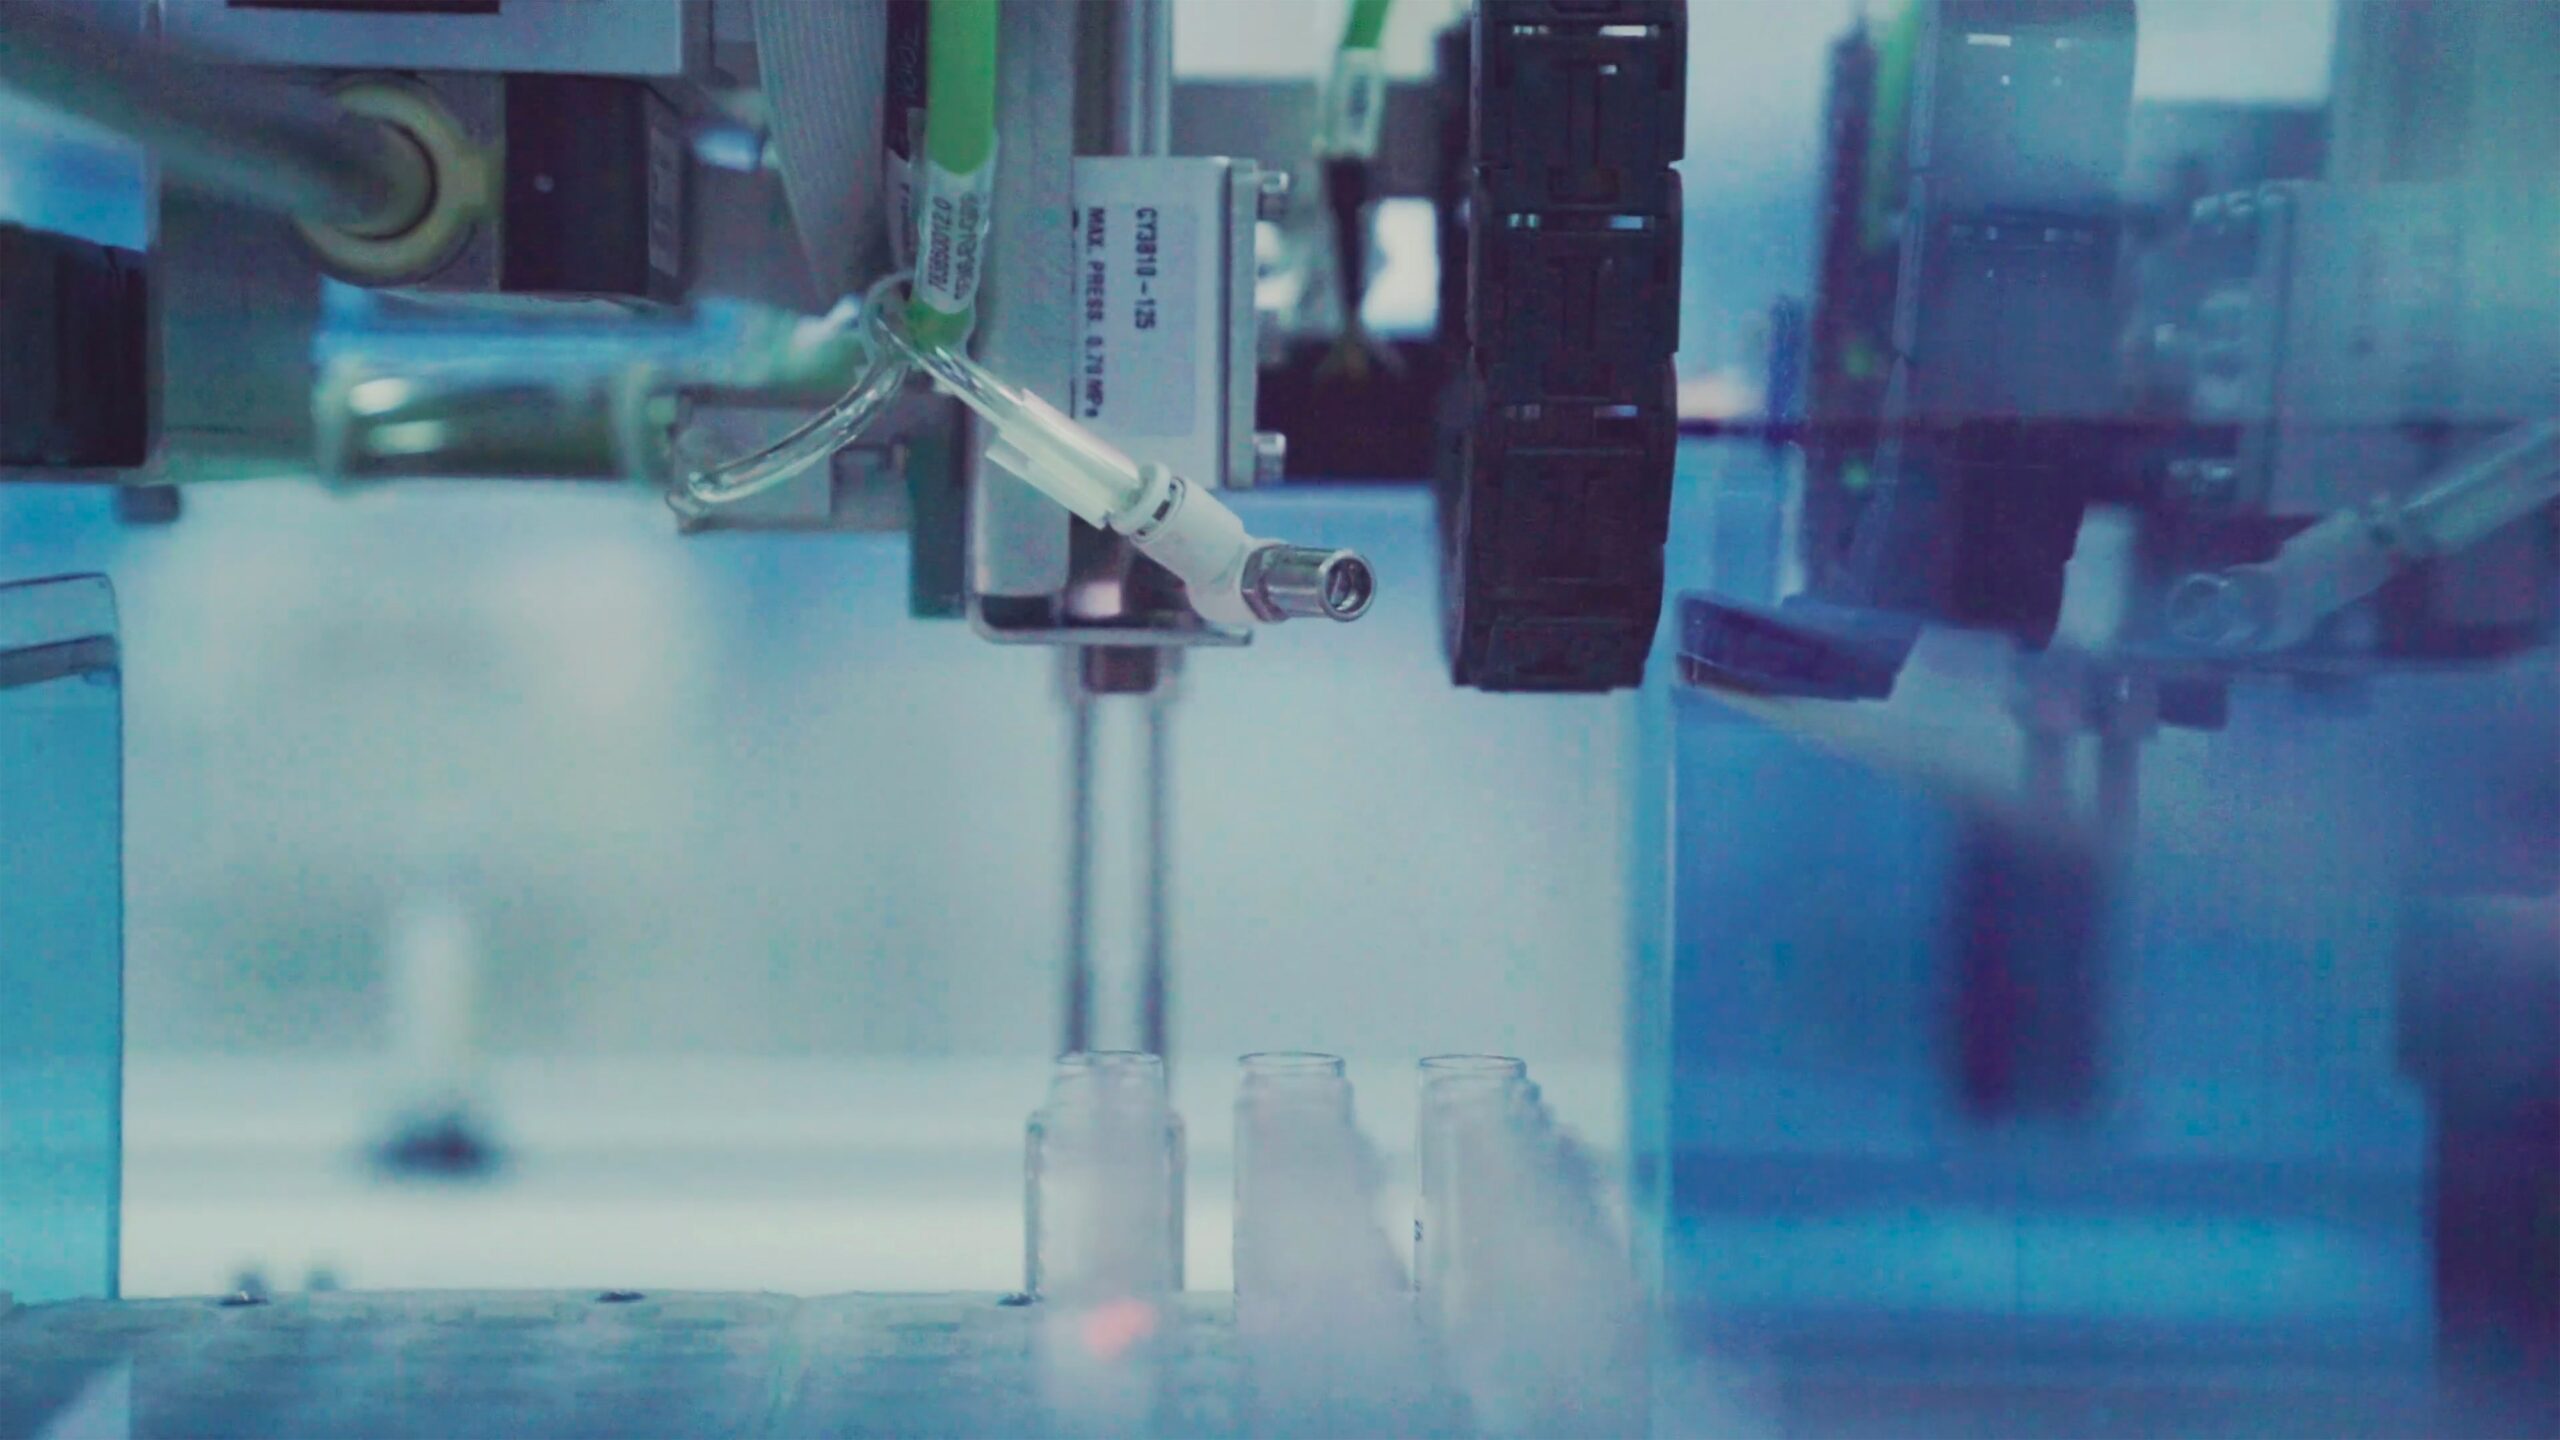

Diagnostyka mikrobiologiczna stanowi fundament w medycynie, przemyśle farmaceutycznym, spożywczym oraz wielu innych sektorach, gdzie precyzja i szybkość analiz mają ogromne znaczenie. Aby sprostać wyzwaniom współczesnego świata, konieczne jest jednak sukcesywne wdrażanie nowoczesnych rozwiązań, takich jak automatyzacja procesów technologicznych. W niniejszym artykule przyjrzymy się temu, dlaczego automatyzacja staje się kluczowym aspektem w diagnostyce mikrobiologicznej i jakie […]